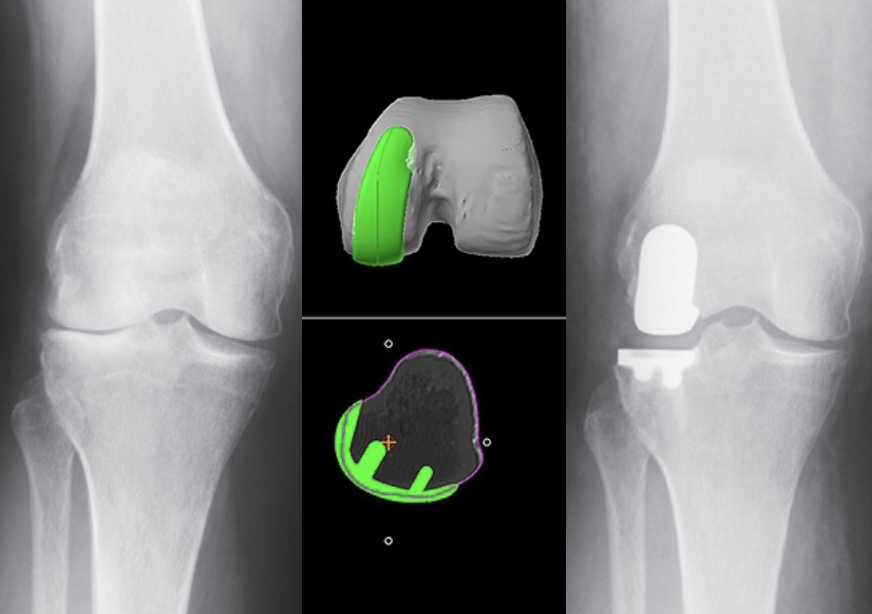

Modelo digital exacto de tu rodilla basado en tomografía computarizada, permitiendo seleccionar el implante ideal y simular el resultado antes de la cirugía.

El brazo robótico MAKO guía cada corte óseo con exactitud de 0.5mm, protegiendo tejidos sanos y optimizando la colocación del componente tibial y femoral.

La artrosis de rodilla avanzada genera dolor constante, rigidez y pérdida de movilidad que afectan tu calidad de vida. Con la tecnología MAKO SmartRobotics®, realizamos reemplazos totales y parciales de rodilla con planificación 3D personalizada y precisión submilimétrica, optimizando la posición de los componentes tibial y femoral para una articulación estable, funcional y duradera.